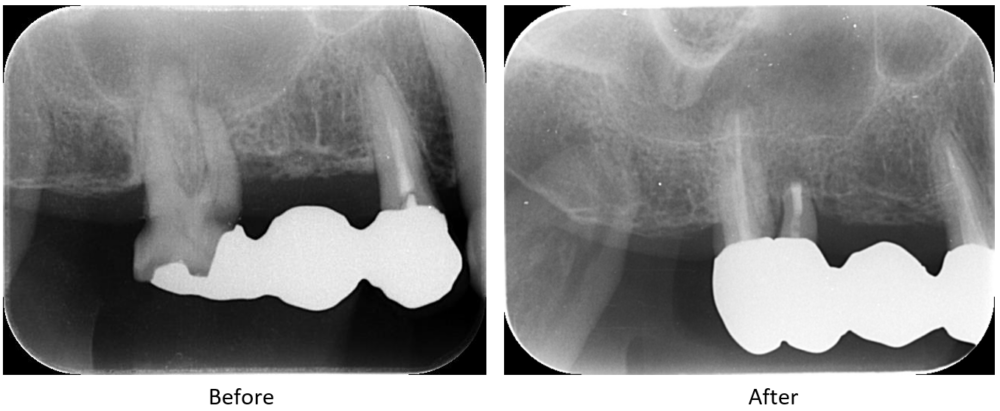

症例1

術前

歯肉は腫脹し排膿していた。

| 医院の診断 | 慢性根尖性歯周炎 |

| ここがこだわりのポイント!☝ | MTAを使用した歯根端切除を行うことで、抜歯を回避することができました。 |